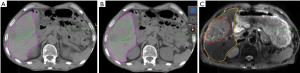

GTVs and liver contours were delineated on all images and IGTVs acquired by merging ten GTVs at all phases of 4DCT images. The GTVs on T2-weighted MRI images were deformably registered to each phase of 4DCT images and labeled –DR. The IGTVDR was obtained by merging the ten GTVsDR after DR. The volume difference among the GTVs, and between IGTV and IGTVDR were compared. All GTVs and liver contours were delineated by the same radiation oncologist, using the same window width and level on 4DCT images (width: 400 HU, level: 40 HU).

GTVs obtained from 4DCT images were increased by an average of 4.23% (P<0.05) after DR, with GTVs following DR of each phase consistent with T2-weighted MRI image basic volume (Table 3, Figures 2,3). After DR all 4DCT image phases GTV were larger than DR before (except CT90, P<0.05).

Comparison of IGTVs before and after DR

The IGTV before DR was 383.89±342.53 cm3, with a 9.67% increase observed following DR (421.02±382.13 cm3), indicating that a significant increase in IGTV volume occurred after DR (P=0.018) (as shown in Table 4).

To assess the accuracy of image registration, we adopted three indicators: overlap degree of the liver, the displacement of the bifurcation point in the portal vein and celiac axis. Our results demonstrated that maximal displacement occurred in the cranial to caudal direction, in keeping with previously published reports (12,13). We used DR technology to analyze the application of 4DCT and MRI images in the delineation of the liver target. Our results revealed that the delineation of GTV size and range based on MRI is significantly greater than 4DCT images. GTV increased by an average of 4.23% (P<0.05) and IGTV volume increased by an average of 9.67% (P<0.05), suggesting that MRI may be a good supplement to CT image information. This not only improves the accuracy of HCC target identification using 4DCT but also may be beneficial in cases where there is a lot of exit noise on the original 4DCT image and failure to identify tumor boundaries.